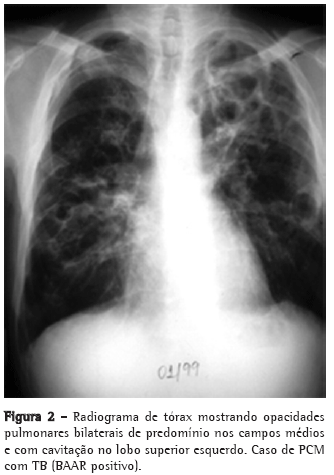

As queixas clínicas, os dados de exame físico e as alterações radiológicas apresentadas por esses doentes, na maioria das vezes, não permitiram a diferenciação segura entre as duas doenças (Figuras 2, 3 e 4).

A PCM acomete muito mais o sexo masculino (15:1), sendo a maioria dos pacientes formada por lavradores ou ex-lavradores com idade entre 30 e 50 anos. Comumente são oligossintomáticos, com poucos achados de exame físico, podendo, no entanto, apresentar exuberantes alterações radiológicas torácicas tanto na radiografia simples quanto na tomografia computadorizada de alta resolução.(11-15)

O acometimento pulmonar é geralmente bilateral, com predomínio nos campos médios e regiões medulares.(16,17)

Por sua vez, a TB acomete ambos os sexos em qualquer idade, com a maioria dos pacientes se apresentando sintomáticos, com exame físico comprometido e alterações radiológicas, em geral, de predomínio em segmentos superiores e posteriores, podendo também ser bilaterais.